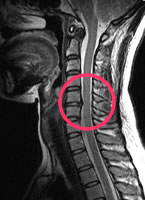

頸椎MRI

頸椎椎間板ヘルニア

ひどい肩こり、頭重感があり脳ドックを受けた。脳に異常はなかったが、頸椎にその原因があった。

手のしびれや首や肩のこり、痛みのある方にお勧めします。

| 頸椎MRI | 11,000円 | 手のしびれ・痛み 首の痛み・肩凝りなど | 頸椎椎間板ヘルニア |